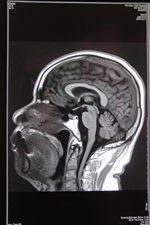

近期,我院今年新购的德国西门子MAGNETOM Avanto I-Class全身磁共振成像系统经过安装调适后正式投入使用。该系统为目前世界上最先进的1.5T磁共振,可以进行全身各部位的高质量扫描。该系统最突出的优势是:成像速度快、图像质量高,扫描覆盖范围大、扫描噪音小。患者在得到最快捷、最准确诊断的同时,还能享受到最舒适安静的检查。

该系统尤其在肿瘤诊断方面具有其突出的优势:一、个是分辨率好;二、反映的特性比较多,有利于临床把握肿瘤的诊断。三、它可以一次性的完成全身的核磁检查,第一次真正做到了高分辨的全身成像。可以很好的评估肿瘤的转移扩散程度,也通过全身的弥散成像使我们了解局部的淋巴结和全身的淋巴结,从其它医院完成的大量的病例来看,Avanto在全身肿瘤的筛查、评估方面准确性非常高。这为我院的肿瘤影像诊断提供了一个新的,有力的武器,为正常人进行磁共振全身疾病筛查带来福音。可真正做到对疾病早发现、早诊断、早治疗,使患者得到优质的医疗服务。